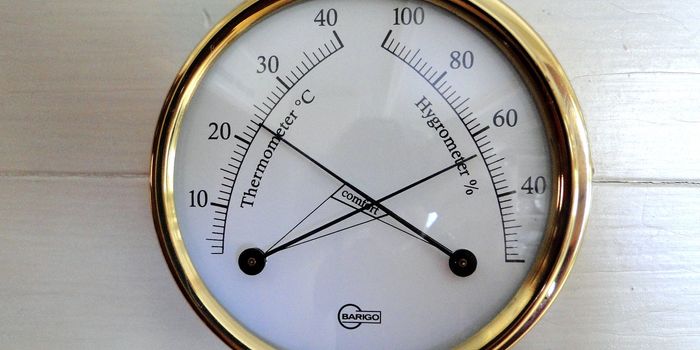

APR 22, 2016Health & MedicineAre mouse research facilities at the right temperature? A recent opinion piece/review published in Trends in Cancer seem ...